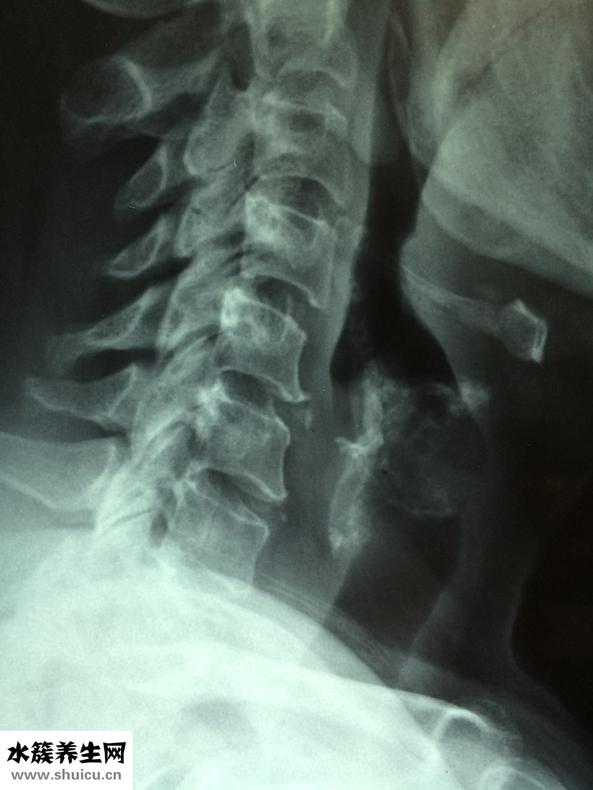

1、最先需要大伙兒了解一下,眩暈癥的病癥有很多,頭昏便是在其中一種,而且很多人都有頭暈眼花的病癥,這主要是頸椎骨及其腰椎間盤退行性變造成的,也有便是椎動脈血管堵塞,腦部的血供不順暢,眼底黃斑神經功能紊亂及其病菌感染等病癥也會造成眩暈癥。因此,對眩暈癥要有一個簡易的了解,而且要到醫院門診去做一些查驗,看一下究竟是什么原因,隨后才好目的性的醫治。